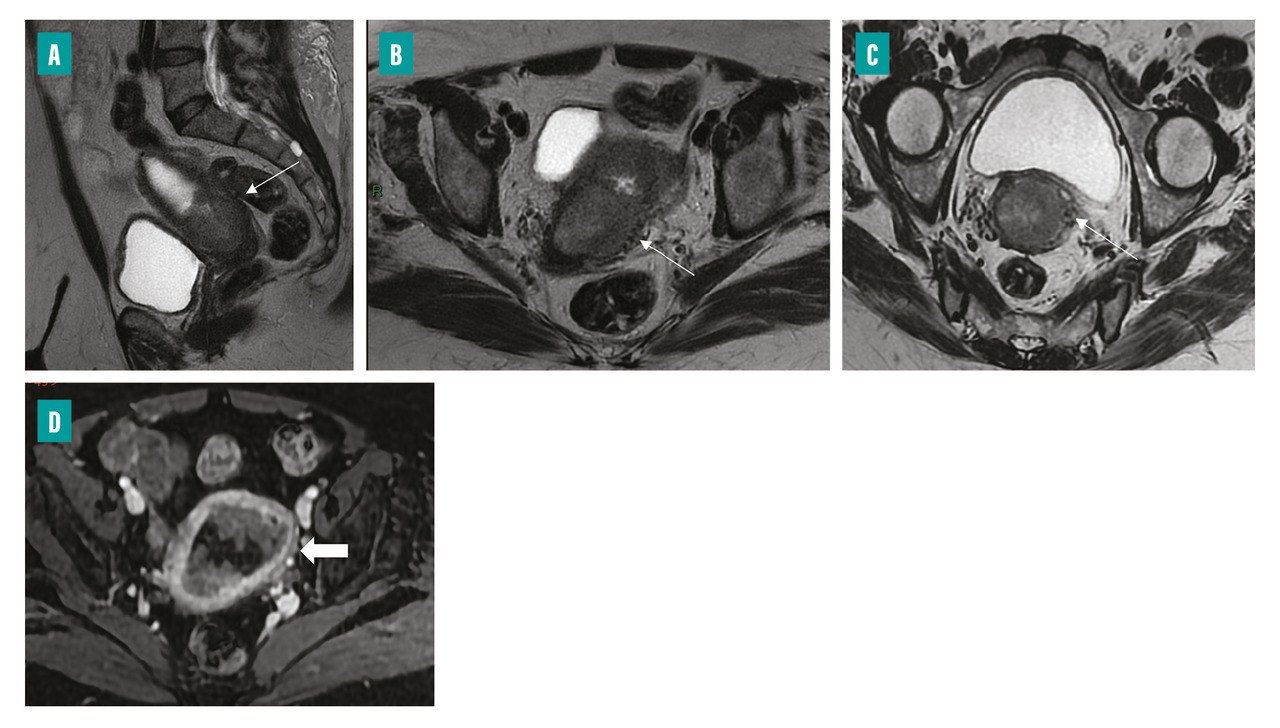

Le bilan d’extension locorégional préopératoire repose sur l’imagerie par résonance magnétique (IRM) pelvienne qui permet de mieux stratifier les patientes selon leur risque. Le protocole d’examen comporte des séquences axiales et sagittales T2, des séquences T1 après injection, dynamiques ou uniphasiques à 2 minutes 30 (temps auquel la différence de contraste entre le myomètre et le cancer de l’endomètre est maximale), et des séquences de diffusion (fig. 1). Ces dernières améliorent les performances de l’IRM dans l’évaluation de l’atteinte myométriale. À ces séquences centrées sur le pelvis s’ajoute une séquence lombopelvienne remontant jusqu’au plan de la veine rénale afin de juger d’une éventuelle extension ganglionnaire lombo-aortique. Le cancer endométrial est en signal T2 intermédiaire (l’endomètre normal étant en hypersignal T2), avec une prise de contraste inférieure à celle du myomètre et un hypersignal de diffusion avec chute de l’ADC (coefficient de diffusion apparent).

Le compte-rendu précise l’élément-clé qu’est le degré d’envahissement myométrial et/ou du stroma cervical, difficile à évaluer cliniquement. L’infiltration myométriale en IRM s’observe principalement sur les séquences pondérées T2, par interruption de la zone jonctionnelle qui est hypo-intense. Après la ménopause, le myomètre s’atrophie et la zone jonctionnelle s’amincit, rendant parfois l’invasion myométriale difficile à estimer. En cas d’infiltration du stroma cervical, il existe une interruption de l’anneau fibreux du col de l’utérus (à l’état normal en hyposignal T2 franc). Cette dernière est visualisée de façon optimale dans un plan T2 perpendiculaire au col (fig. 2).

Certains éléments peuvent par ailleurs orienter vers le type histologique ; ainsi, un aspect plus hétérogène sur les différentes séquences et un petit axe supérieur à 24 mm plaide en faveur d’un cancer de sous-type non endométrioïde.6

L’IRM occupe donc une place déterminante et permet d’anticiper la nécessité d’une exploration ganglionnaire, le risque d’atteinte ganglionnaire augmentant avec la profondeur de l’extension au niveau du myomètre et avec le type histologique.